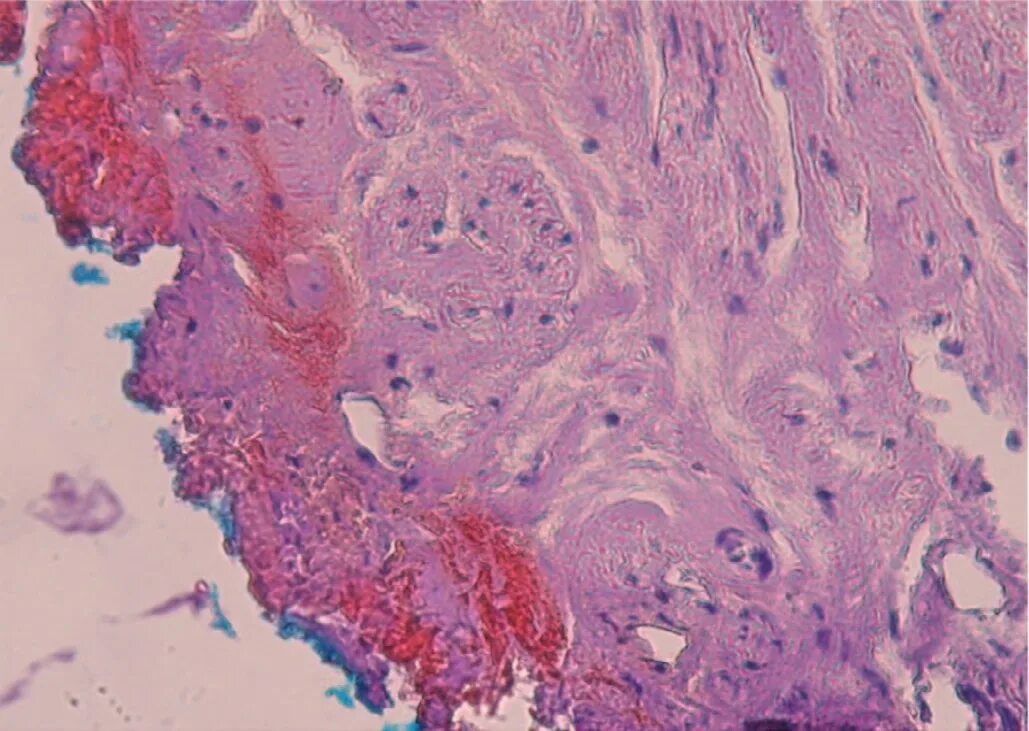

Колликвационный некроз это